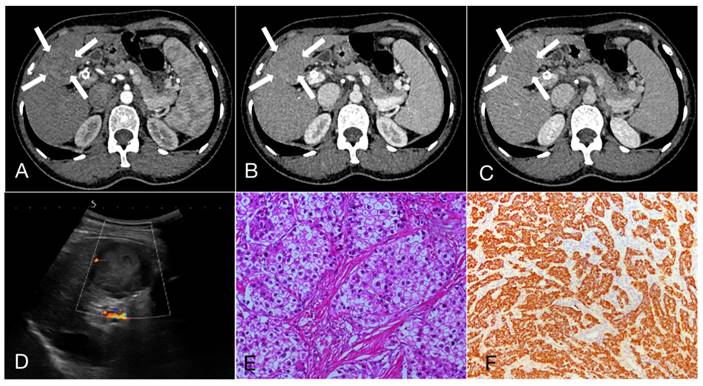

Figure 2

A 47-year-old female patient with Intrahepatic cholangiocarcinoma (6.9cm×5.6cm). A, B, C. Rim arterial phase hyperenhaancement (APEH) (arrow) in the arterial phase, followed by early portal venous phase washout; D. Ultrasound demonstrated a moderately echogenic nodule in the segment 4 of the liver, and the dilated intrahepatic bile ducts can be observed (arrow); E. Hematoxylin and eosin staining, ×200; F. The immunohistochemical marker CK7, ×100.

As shown in Table 3, 47.3%, 22.3% and 30.4% of HCC showed APHE, partial APHE, and rim APHE in the arterial phase, while the percentages of ICC with these imaging features were 30.6%, 37.1%, and 32.3%, respectively (X2 = 13.374, P=0.001). Hypo-enhancement, delayed enhancement and iso- or hyper-enhancement in the portal and equilibrium phases of CT were observed in 37.6%, 19.5% and 42.9% of HCC, and 58.1%, 25.0% and 16.9% of ICC, respectively. Statistical significance of image features in the portal and equilibrium phases was observed between the two groups (X2=11.222, P=0.001). In brief, peripheral rim-like APHE was more commonly observed in ICC, while early washout in the portal venous phase and equilibrium phase was also more prominent (Figure 1, 2).